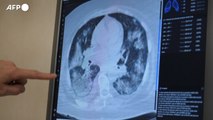

Non solo long-Covid, il long-raffreddore dura 11 settimane